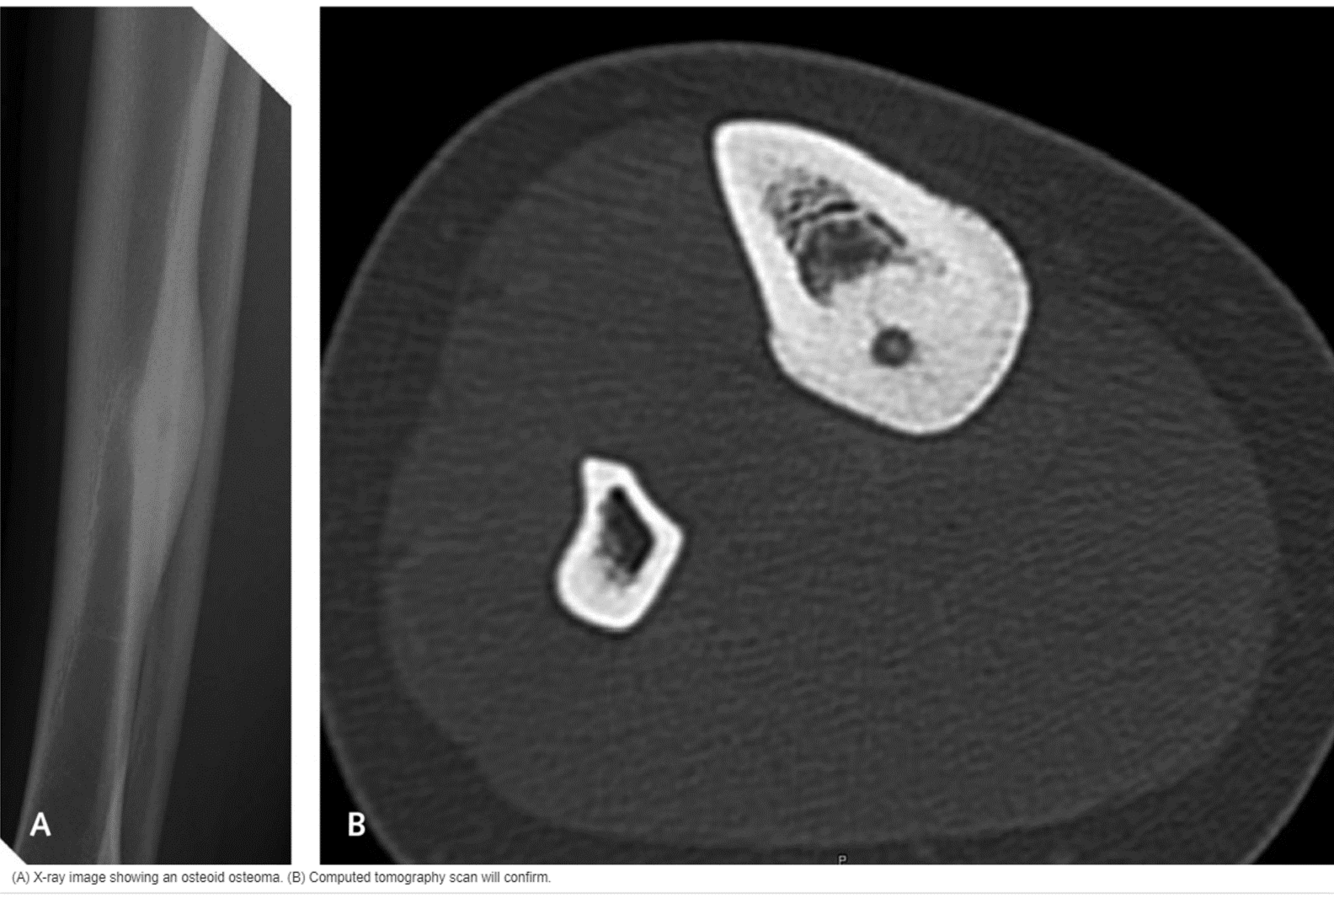

• CT: used to confirm osteoid osteoma

What is an osteoid osteoma?

• painful, self-limiting benign bone lesion

• caused by an accumulation of osteoblasts located in the cortex of bone

X-ray and CT image of osteoid osteoma…